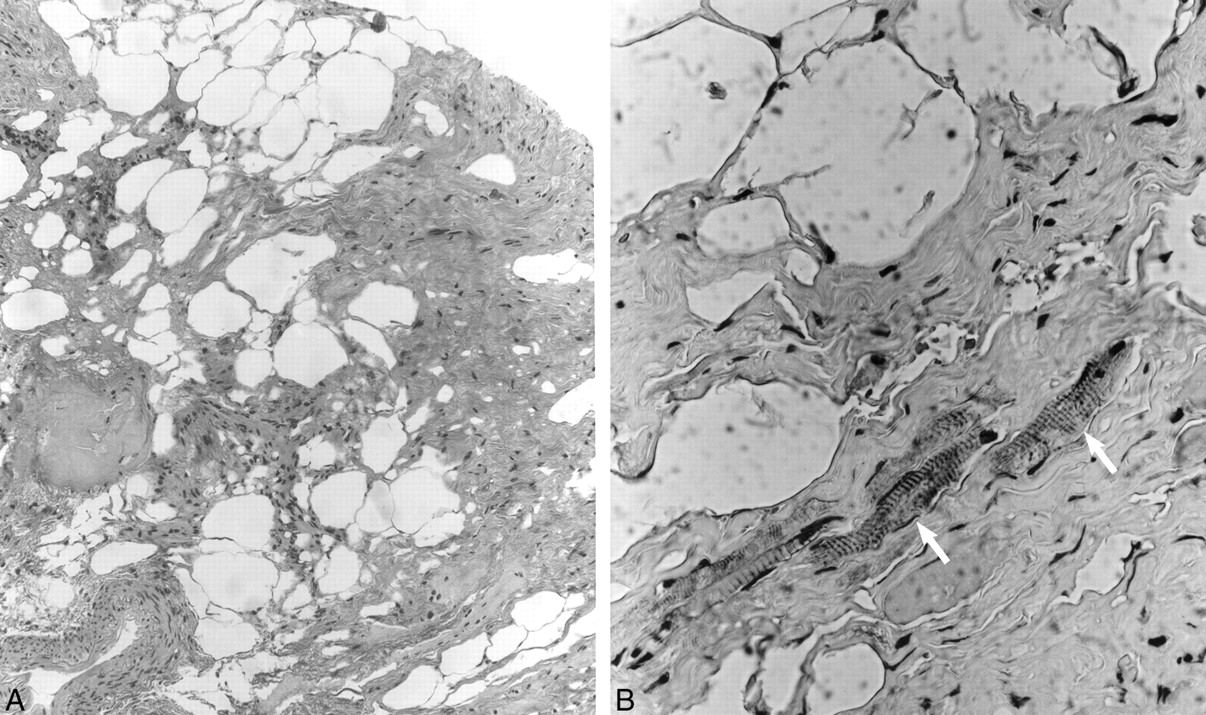

Left subtemporal craniotomy with microscopic exploration revealed a 1-cm fatty nonaneurysmal mass arising from the oculomotor nerve 1.5 cm distal to the left root entry zone. The mass was densely adherent to both the left cerebral peduncle and basilar artery. The findings of intraoperative frozen pathologic examination indicated hamartoma. Because of concern about inducing a permanent oculomotor palsy, a complete resection was not attempted. Nevertheless, postoperatively the patient had a third nerve palsy that slowly resolved over subsequent follow-up examinations. Microscopic histopathologic examination using hematoxylin and eosin (H&E) and immunoperoxidase preparations (anti-S100, anti-desmin, anti–muscle-specific actin, and anti-neurofilament) was performed. Low-power H&E stain evaluation (Fig 4A) demonstrated dense collagen bundles admixed with fat cells, nerve filaments, and blood vessels. Higher power immunoperoxidase anti-desmin preparation (Fig 4B) revealed scattered skeletal muscle fibers interspersed within the dense collagenous tissue. The identification of mature representatives from all three tissue lines and absence of malignant features permitted a final tissue diagnosis of mature teratoma.

A, Low-power (original magnification ×100) H&E photomicrograph demonstrates dense collagen bundles admixed with fat cells, nerve filaments, and blood vessels.

B, Higher power (original magnification ×400) immunoperoxidase (anti-desmin) preparation reveals scattered skeletal muscle fibers (arrows) interspersed within the dense collagenous tissue, features consistent with teratoma.